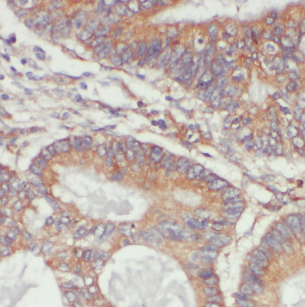

Immunohistochemistry of paraffin-embedded human colon cancer using FNab04905(LYPLA1 antibody) at dilution of 1:100 IP Result of anti-LYPLA1 (IP:FNab04905, 4ug; Detection:FNab04905 1:500) with mouse brain tissue lysate 4000ug.